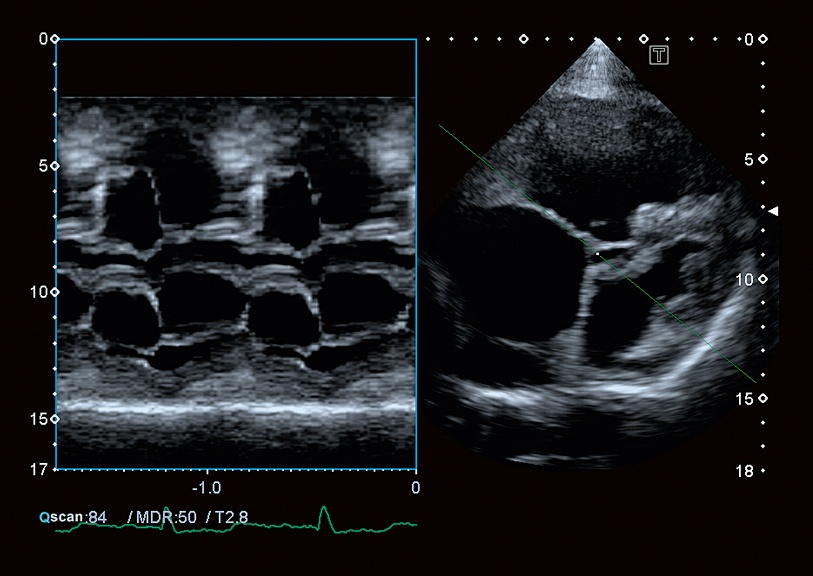

Consistently acquire a correct M-mode image.

Flex-M Mode

Aplio CV's Flex-M functionality enables acquisition of online or off-line anatomically-corrected M-Modes on patients with technically difficult images.